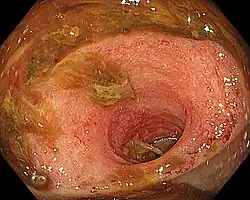

Ileitis caused by capecitabine.

Ileitis is an inflammation of the ileum, a portion of the small intestine. Mycobacterium tuberculosis infection may mimic Crohn's disease Ileitis.[1] Ileitis may be linked to a broad range of illnesses, such as sarcoidosis, amyloidosis, ischemia, neoplasms, spondyloarthropathies, vasculitides, drug-related conditions, and eosinophilic enteritis.[2]`